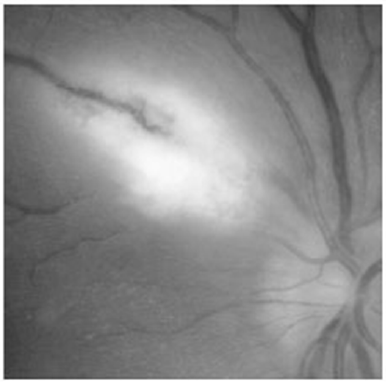

Acerca do descolamento de retina tracional mostrado na figura acima, assinale a alternativa correta.